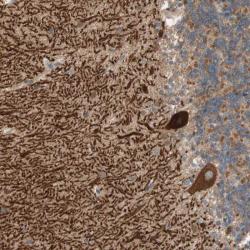

Supportive validation

- Submitted by

- per

- Main image

- Experimental details

- Immunohistochemical staining of human cerebellum shows strong cytoplasmic positivity in purkinje cells.

- Validation comment

- Staining pattern consistent with experimental and/or bioinformatic data.